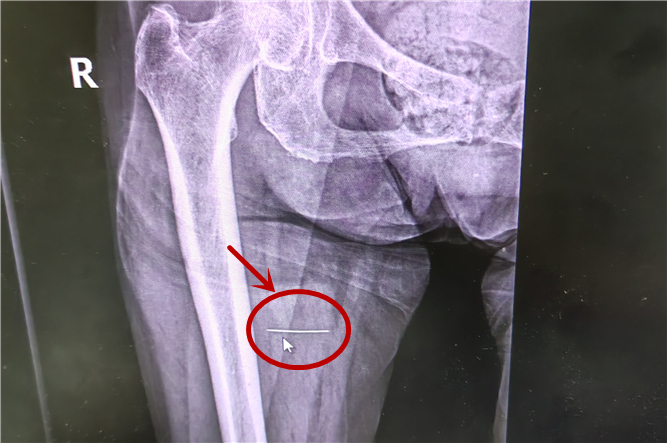

入院后進(jìn)行了DR檢查,驗(yàn)證了大家的猜想:發(fā)現(xiàn)右大腿異物,顯示這根縫衣針進(jìn)入了大腿的肌肉層。

可怕的是幾次拍片顯示,這枚鋼針竟然隨奶奶的活動(dòng)在體內(nèi)肆意游走。

手術(shù)前的最后一次拍片顯示,“縫衣針”位于大腿中段大收肌內(nèi),針尖位于股深動(dòng)脈處,針尾在坐骨神經(jīng)處。手術(shù)時(shí)可見右大腿近端內(nèi)后側(cè)約1毫米針孔,周圍皮膚充血。手術(shù)中,發(fā)現(xiàn)異物在肌肉內(nèi)移動(dòng)幅度大,尋找困難,克氏針橫堅(jiān)C臂定位照相不宜定位!